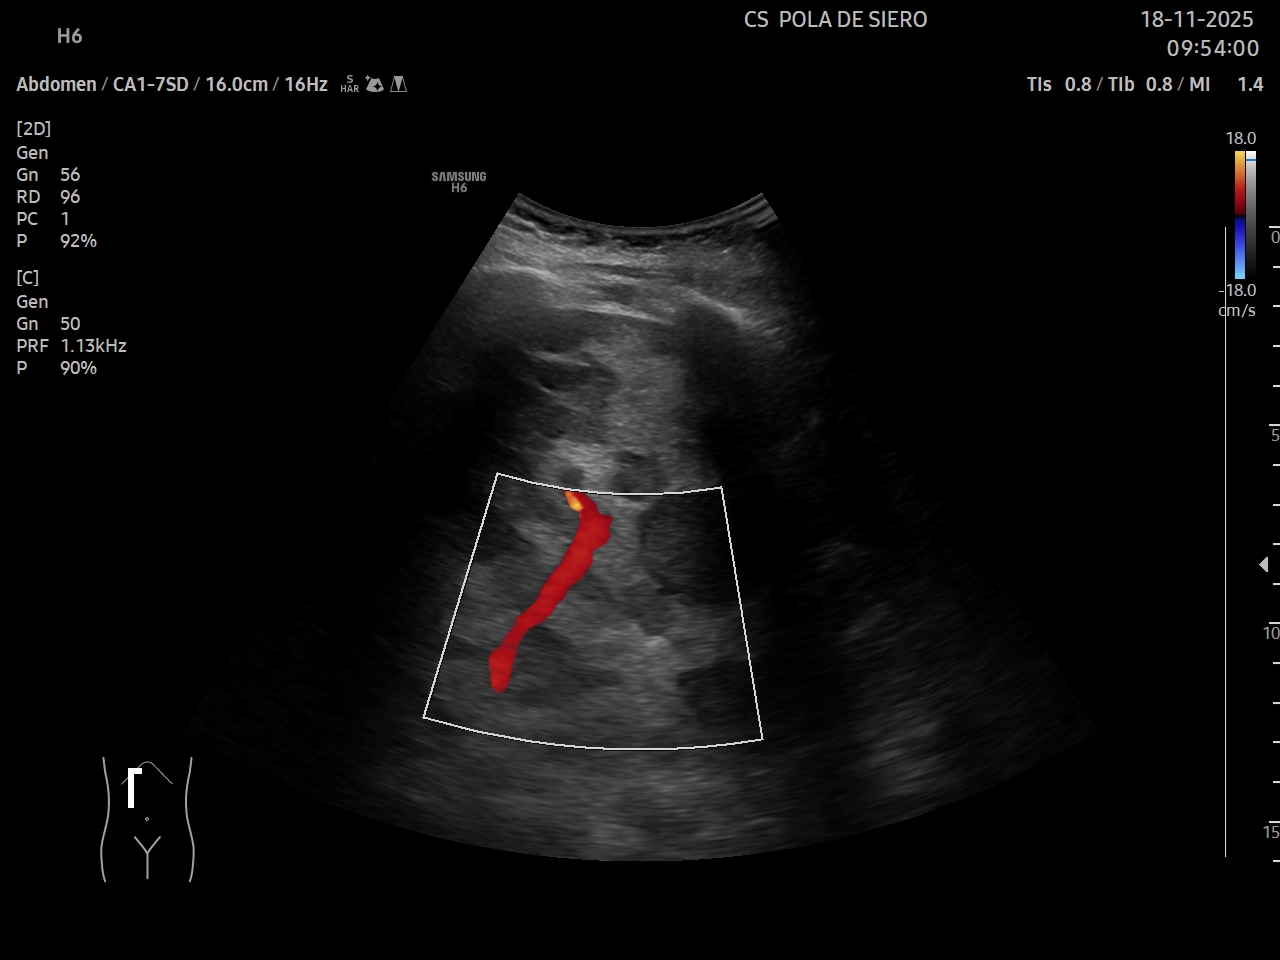

Ecografía clínica: múltiples imágenes hipoecoicas que afectan todo el parénquima hepático, vesícula alitiásica. Porta desplazada, permeable. Flujo hepatópeto y riñones normales. Bazo de tamaño normal. Vejiga no replecionada. No líquido libre.

Juicio clínico: metástasis hepáticas múltiples.